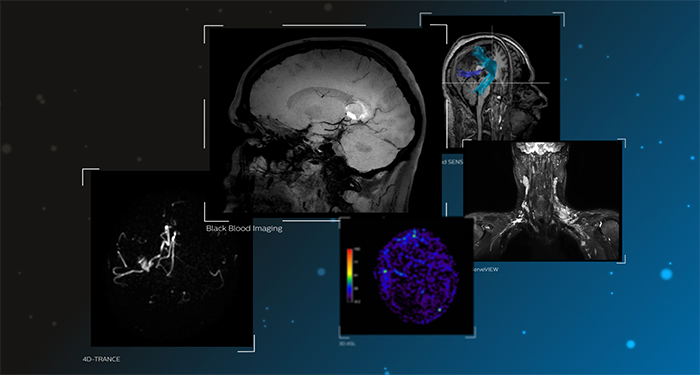

Discover our neuro applications

Clinical cases from nearly every anatomy Explore 100+ clinical cases from your peers around the globe, that showcase how Philips MR digital technology strengthens your imaging needs.